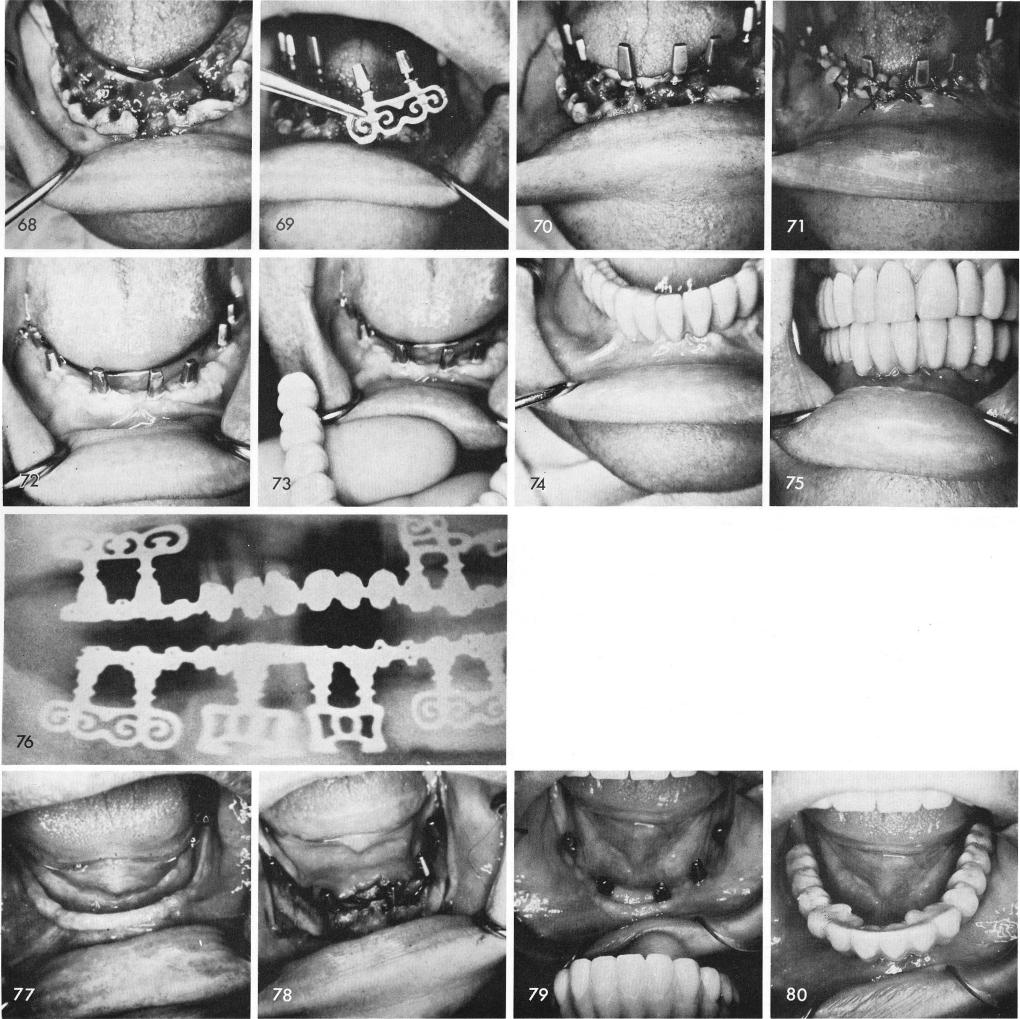

In this edentulous mandible with several fresh sockets, fig. 68, some of my newer designed implants were used, figs. 69, 70, 71, 72, to support a full arch fixed prosthesis, figs. 73, 74, 75. The post-operative x-ray, fig. 76.

Even in a totally edentulous mandible that exhibits a knife-edge ridge and shallow ridge, fig. 77, blades can usually be satisfactory, fig. 78.

Because of the severe vertical bone loss the fixed prosthesis was fabricated with an extremely long pink gingival portion both anteriorly and posteriorly, fig. 79. In this manner the vertical dimension was maintained and the teeth did not look so long and grotesque, figs. 80, 81, 82, 83.